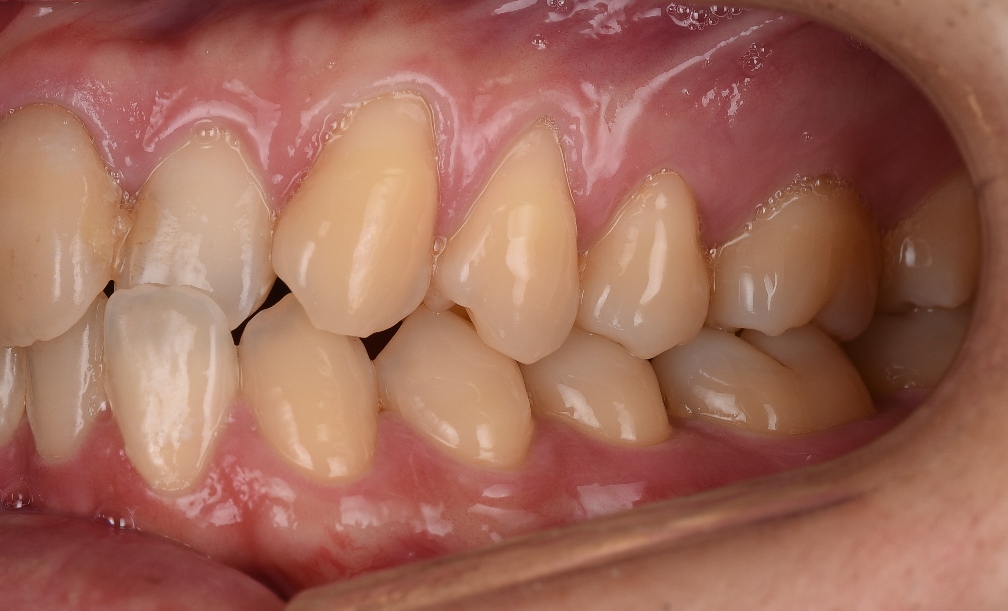

こんな感じで、歯茎が下がり、根っこが見えてしまい歯ブラシも出来ない状態です。

ここにプラスチックを詰めていく事は「応急処置」にしかならず、

根本的には歯肉を少しだけ移植するだけで